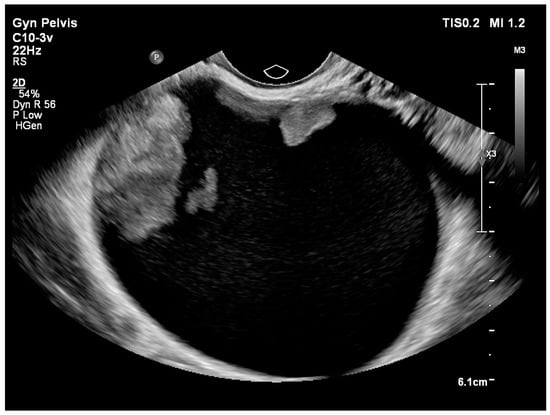

| Cystic (Figure 3) | 24 (28.2) |